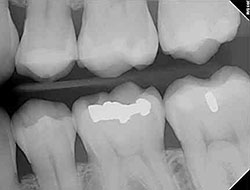

Due to rapid growth and changes in children, x-rays may be needed more frequently than in adults. Digital x-rays allow for safer diagnosis with less radiation than traditional x-rays. It may also allow us to detect dental decay at its earliest stage when treatment can be avoided, or require less invasive techniques. Using digital radiography provides 90 percent less radiation.